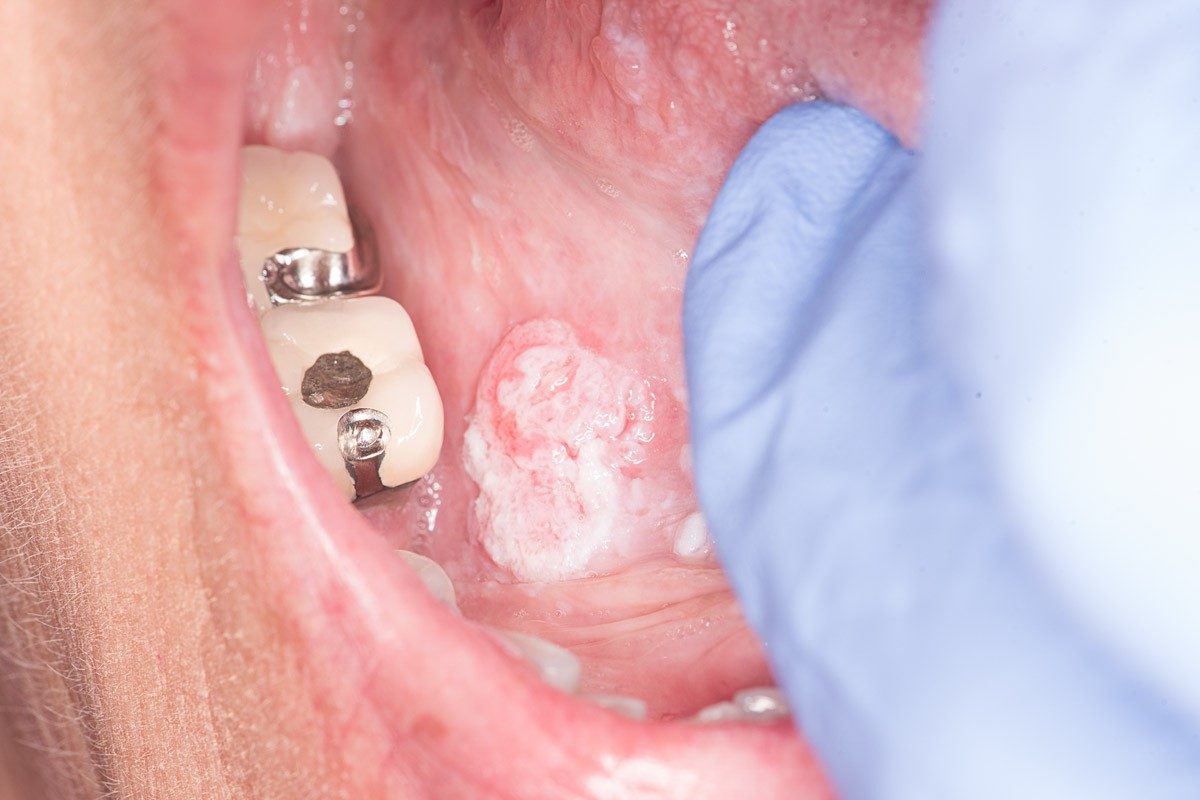

Oral cancer pictures

A cancerous growth behind the last molar.

Cheeks: Watch for small ulcers or tumors, as well as redness or bleeding.

Gums: Look for redness, bleeding or lumps, especially without any injury to those areas. These can be in the bed of a tooth or on the surface of the gums.